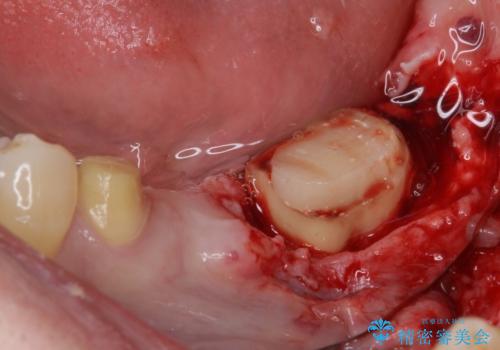

診察を行ったところ、奥の土台になっている歯は神経組織が失活しており、根尖部に病変があり、そこが原因で痛みを生じている状態でした。

根管治療を行うためにブリッジを除去したところ、むし歯が歯肉の奥深くにあまで及んでいたため、歯周外科処置によりむし歯が歯肉縁より浅い位置へと改善することとしました。

まずは奥歯の痛みを改善し、その後矯正治療を行い、最後にオールセラミックブリッジによる補綴治療を行うこととしました。